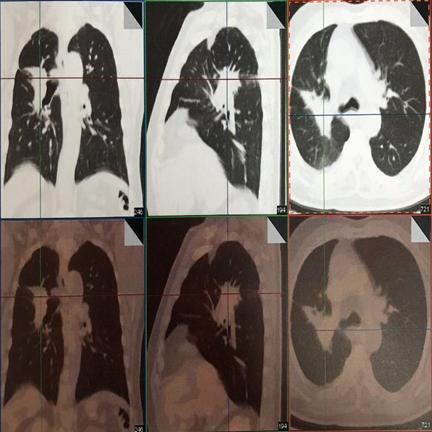

治疗后5年复查,患者偶有咳血,局部病灶纤维化改变

治疗后11年复查,无明显活动后 气喘 。